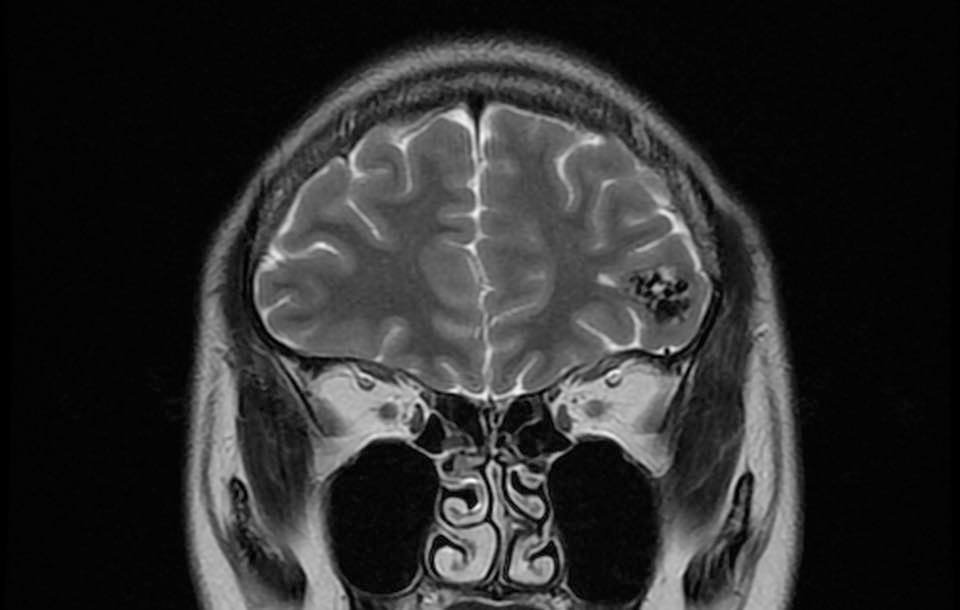

病人….被另一名曾經嚴重腦出血性中風(腦動脈瘤破裂以致嚴重的蜘蛛綱膜下腔出血及曾經瞳孔放大和深度昏迷…其後完全康復)的病人介紹…..帶MRI 底片到我診所尋求第二醫療諮詢….. 其時心情亦愉快…….直到….看了MRI 影像後…..我告訴她真正的MRI檢查結果……她的左前腦額葉上….有一個3cm大的腦動靜脈畸形血管瘤(AVM).. ….亦有最近出過血的跡象…可能是她失去意識和腦癇症的原因。

兩天後….在私家醫院為她做診斷式的動態腦血管造影來確定䐉血液的流動模式後,再進行了4 小時的顯微鏡手術….AVM的計時炸彈完全切除……..在AVM旁邊的腦部亦能看到血鐵黃素的舊有殘留血液。手術後兩天出院。